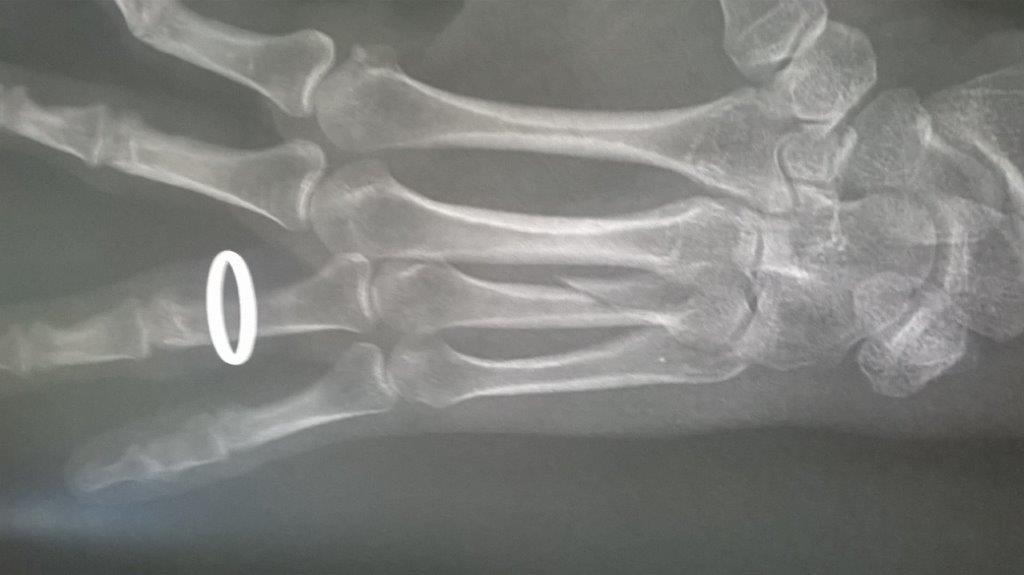

Résultat : fracture de la main gauche

Fichier(s) joint(s):

WP_20170914_001.jpg [ 47.5 Kio | Vu 29221 fois ]

Mais je confirme que ma saison de triathlon s'achève aujourd'hui. Main gauche immobilisé. Je suis au regret de déclarer forfait pour Paladru et d'abandonner les Mixirilliettes à leur triste sort